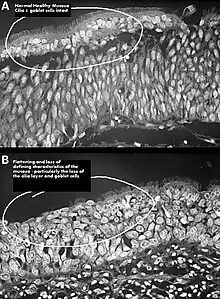

One possible cause may be changes to the nasal mucous membrane and to the nerve endings in the mucosa resulting from chronic changes to the temperature and humidity of the air flowing inside the nose, caused in turn by removal or reduction of the turbinates.[4][5] Direct damage to the nerves may be a result of surgical intervention; however, as of 2015, there is no technology that allows the mapping of the sensory nerves within the nose, so it is difficult to determine whether this is causative of ENS.[4] Investigators have been unable to identify consistent diagnostic or precipitating features, psychological causes leading to a psychosomatic condition have been proposed.[4][9][10][12]